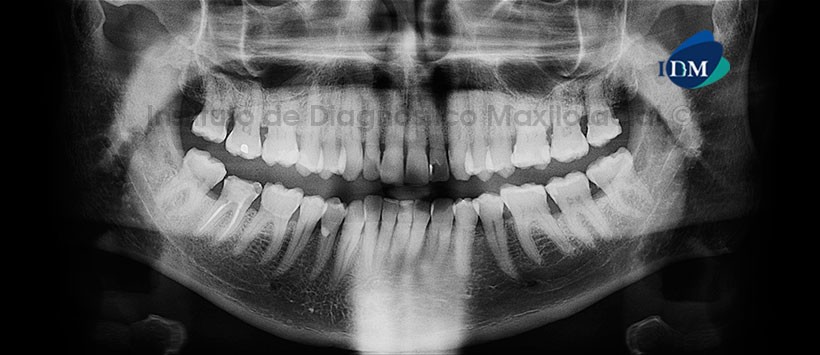

Paciente de sexo masculino de 45 años acude al Instituto de Diagnostico Maxilofacial (IDM) para evaluación de la pieza 46.

A la evaluación de la radiografía panorámica (ortopantomografia), siendo lo más característico la presencia de material de obturación de conductos de la pieza 46 así como material de restauración cameral. (Figura 1)